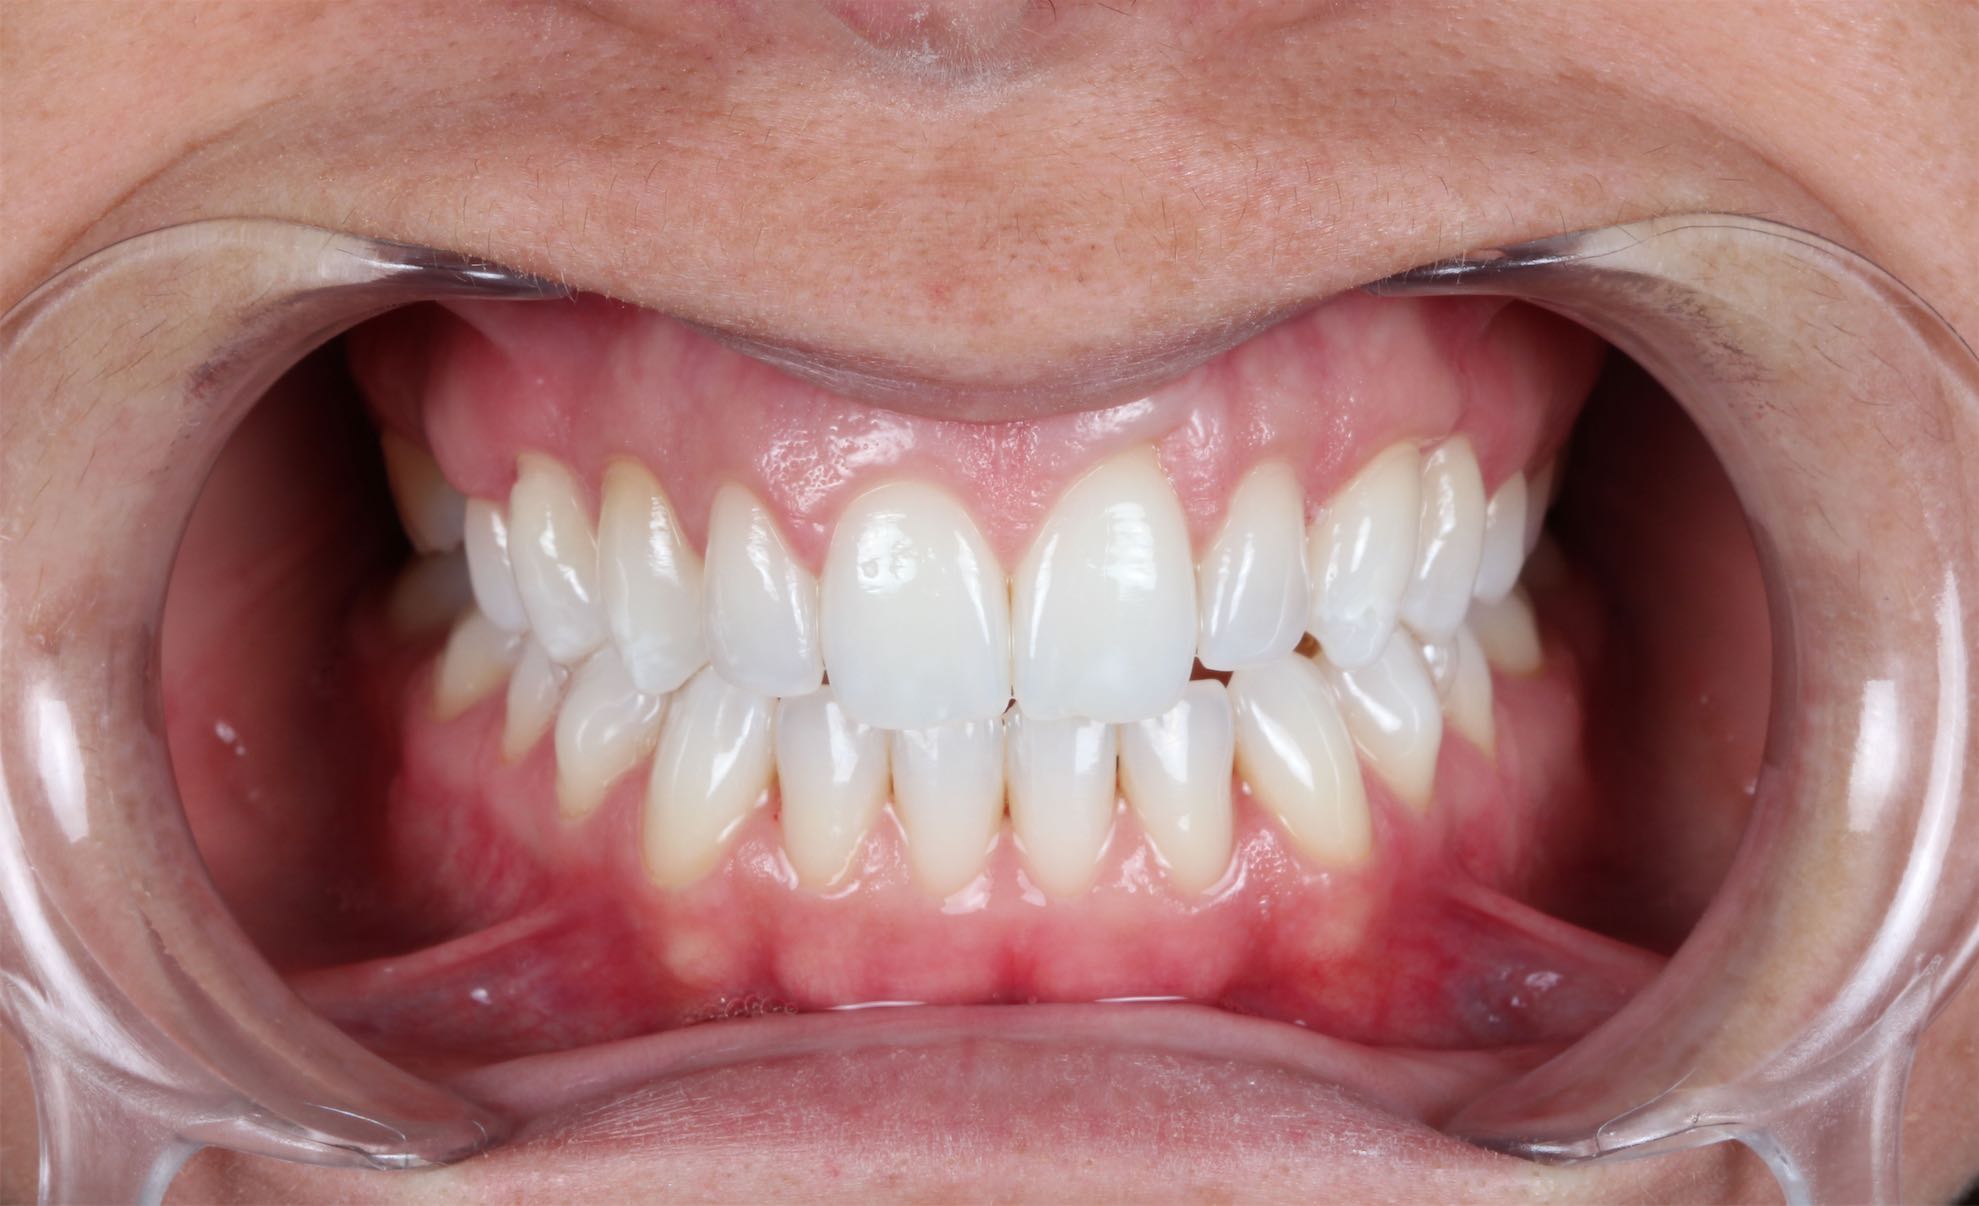

Ortodoncia

BeforeAfter